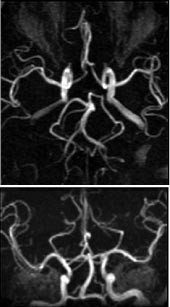

Bildeopptaket kan gjøres med to- eller tredimensjonal teknikk (henholdsvis 2D- eller 3D-innstrømnings-MRA). Ved 2D-teknikken registreres de induserte strømsignalene fra en tynn skive om gangen, og i løpet av et bildeopptak dekkes den aktuelle anatomien av mange skiver kant i kant eller med en viss overlapping. Denne teknikken er sensitiv for langsom (venøs) blodstrøm fordi det i hvert snitt bare er en kort blodsøyle som behøver å erstattes av friskt blod utenfra (fig 2). Ved 3D-teknikken registreres signalene fra et større, avgrenset volum, og teknikken er derfor avhengig av høyere (arteriell) blodstrømshastighet for å fornye blodet i de dype deler av volumet. 3D-innstrømnings-MRA gir best romoppløsning og er mer egnet enn 2D-teknikken til å vise slyngede kar (fig 3).

Fasekontrast-MRA

Fasekontrast-MRA (2D eller 3D) gir i likhet med innstrømnings-MRA «hvite» blodårer fordi blodet beveger seg. De to teknikkene er likevel prinsipielt svært forskjellige. Ved innstrømnings-MRA er gråtonen i bildene bestemt av styrken til det induserte strømsignalet. Ved fasekontrast-MRA er gråtonen i hvert bildeelement (piksel) bestemt av signalenes fase (4). Det er mulig å gjøre bildeopptakene på en slik måte at signalene fra alt stasjonært vev får én felles fase, mens alt blod som beveger seg, får en avvikende fasevinkel. På den måten kan man selektivt fremstille blodårene, og bare dem. Stasjonært vev gis ingen gråtone og blir helt svart i bildet, mens blod som strømmer, får en gråtone eller hvithet bestemt av blodstrømshastigheten (fig 4). Avhengig av opptaksteknikken vil en viss blodstrømshastighet gi maksimal hvithet, mens både lavere og høyere blodstrømshastigheter vil fremstilles med svakere intensitet. For å få optimal fremstilling av blodårene med fasekontrast-MRA, må man derfor på forhånd kjenne til den omtrentlige blodstrømshastigheten i de aktuelle blodårene. Fasekontrastteknikken kan også benyttes til å måle blodstrømmens hastighet.